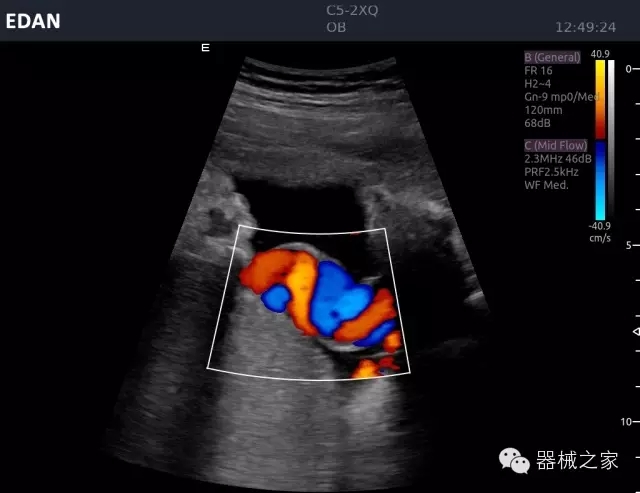

經(jīng)典產(chǎn)品:Acclarix AX8

臨床圖片賞析

睪丸低速血流

臍帶血流

頸動脈頻譜

產(chǎn)品特點

·新視界、高效能、新體驗;

·別具匠心的獨特設(shè)計、創(chuàng)新工作流、強大的功能組合以滿足POC圖像的需求;

·15英寸高分辨率顯示器;

·10.1英寸防指紋觸摸屏;

·獨一無二的觸控式軌跡球;

·超聲模塊的便攜式設(shè)計;

·128物理通道;

·UPS持續(xù)供電;

多項前沿圖像技術(shù)

·復(fù)合成像 波束合成 頻率復(fù)合 噪聲抑制等;

穿刺針增強技術(shù)

·顯著增強針體 清晰識別結(jié)構(gòu)、位置等比鄰關(guān)系;

多種成像模式

·梯形成像 寬景成像 3D成像 特征成像等;

CFDA注冊證編號

·粵械注準20152230912